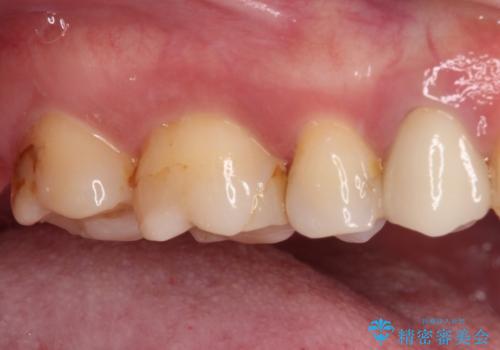

- 奥歯の詰め物や周辺の歯が欠けてしまったとのことで来院された患者様です。

上顎は、元々の詰め物が小さく、欠けた範囲も大きくなかったため、セラミックインレーにて修復治療を行うこととしました。

一方下顎は、元々のむし歯の範囲が広かったため、長期的な予後を踏まえ、セラミッククラウンにて補綴治療を行うこととしました。